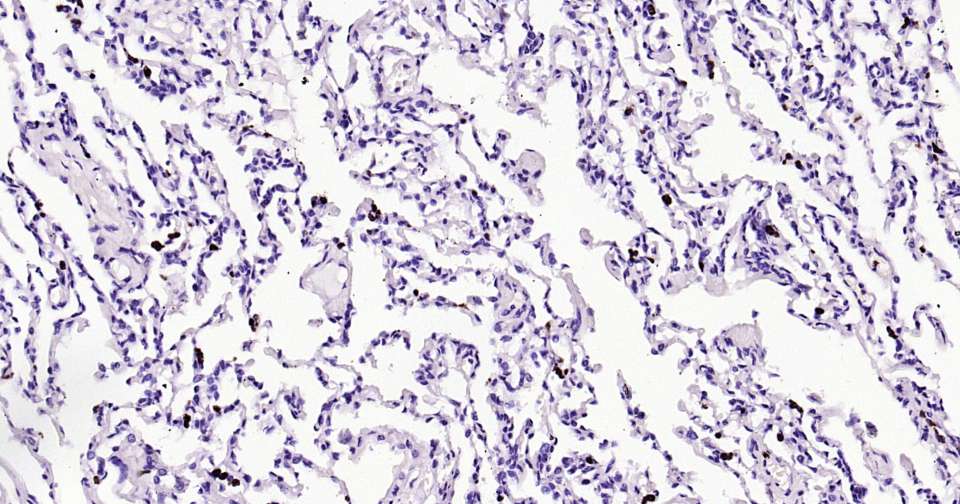

Immunohistochemical analysis of paraffin embedded human colon cancer tissue slide using IHC0388H (Human Granzyme B Kit).

Immunohistochemical analysis of paraffin embedded human colon tissue slide using IHC0388H (Human Granzyme B Kit).

Immunohistochemical analysis of paraffin embedded human lung tissue slide using IHC0388H (Human Granzyme B Kit).

Immunohistochemical analysis of paraffin embedded human tonsil tissue slide using IHC0388H (Human Granzyme B Kit).